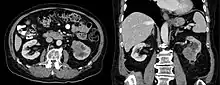

Collecting duct carcinoma in computed tomography